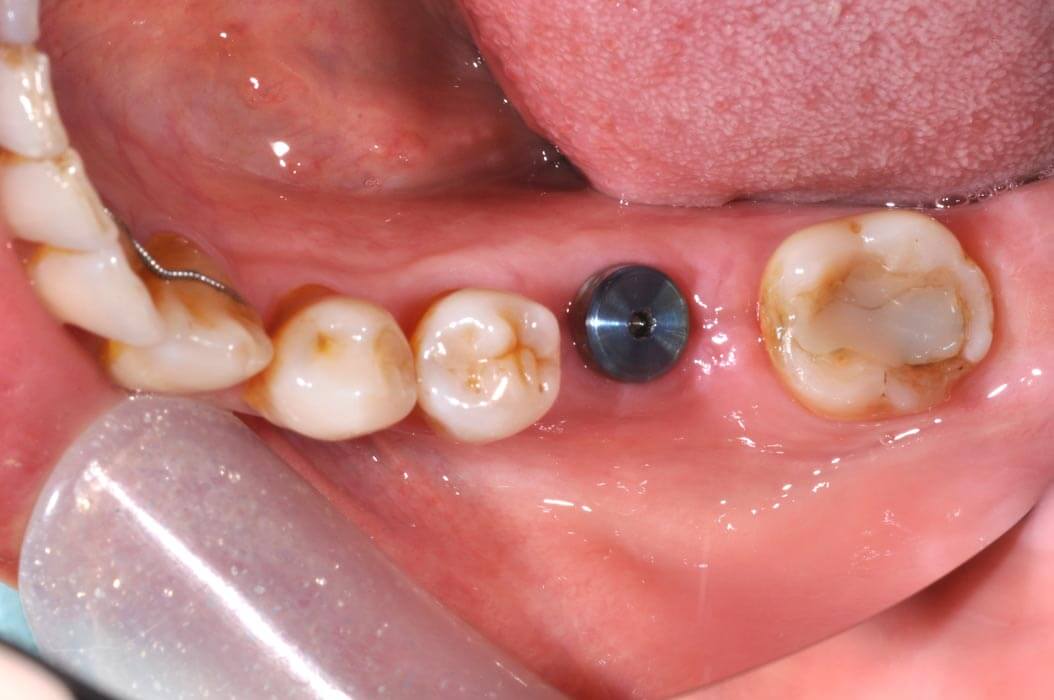

植牙過程一般分為兩個階段:第一階段先將植體放置於骨內,讓植體與骨結合;第二階段接出柱心並裝上假牙。整個療程約需3至6個月。

正式植牙假牙安裝

全瓷植牙假牙安裝,治療完成。正式植牙假牙有著比較多的細節,顏色與形狀也像真牙般逼真。

植牙全瓷牙冠

植牙後